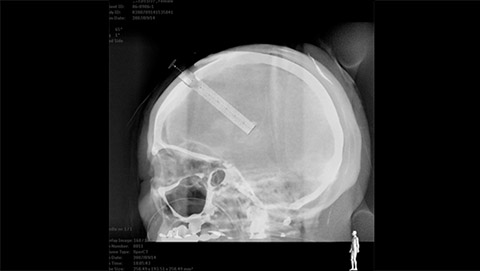

VasoCT visualizes small intra-cranial devices in vessel context with unmatched spatial resolution. Metal Artifact Reduction decreases streaking artifacts as from coil mass close to intra-cranial devices.

VasoCT (Allura X-ray system with dedicated EPX settings + XperCT + intravenous contrast injection) provides high-resolution imaging of intracranial arteries to help visualize location, size, and direction of an occlusion in case of Ischemic Stroke.